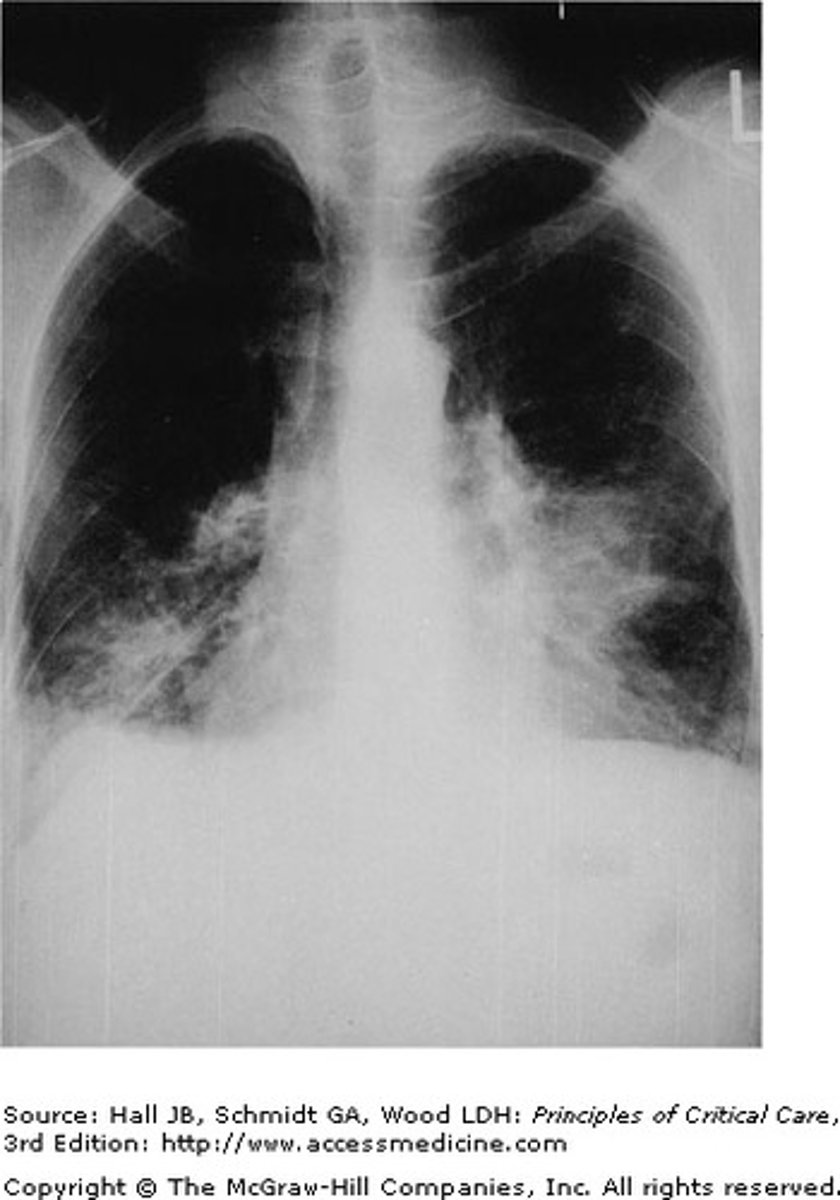

A 24-year-old female HIV-positive patient, who is not currently on medication, presents to the emergency department with acute dyspnea, tachycardia, fever, nonproductive cough, and a room air oxygen saturation of 92%. She admits feeling poorly for the past five days. A physical exam reveals bilateral basilar crackles. An x-ray reveals the image shown. What is the most likely causative organism of this clinical picture?

Pneumocystis is an opportunistic fungal infection of immunocompromised patients, most frequently seen in patients with untreated HIV/AIDS. Patients often present with fever, dyspnea, a nonproductive cough, decreased arterial oxygen pressure, and tachycardia. Lung auscultation may reveal adventitious sounds, but may also be without abnormality. Chest x-ray results classically include bilateral diffuse infiltrates with perihilar involvement. Although the other etiologies are associated with pneumonia, and may be seen in immunocompromised patients, pneumocystis pneumonia occurs in up to 80% of untreated HIV patients and is a leading cause of death.